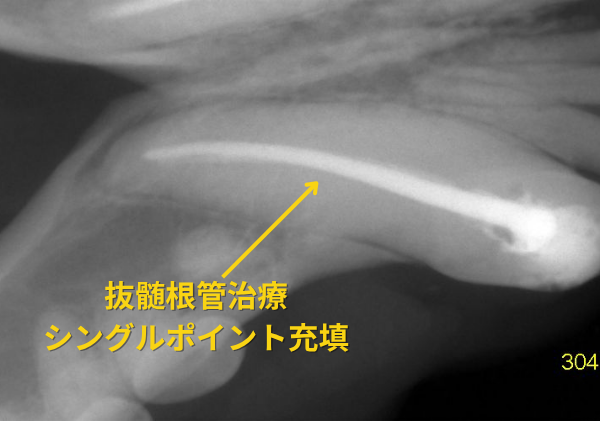

1週間前に、雷に興奮してケージにぶつかり、下顎の両犬歯が折れて、柴犬が来院しました。両方の犬歯は、エナメル質と象牙質が折れ、歯髄が露出していました。抜歯か歯を残す治療が検討されました。下顎犬歯の外科的抜歯は、患者への侵襲性が高く、顎が弱くなるといった副作用もみられるために、歯を残す根管治療(歯内治療)を行いました。

根管治療(歯内治療)とは、炎症の原因となる歯の中の歯髄と炎症物を取り除き、根管を洗浄する処置です。 AIモーターとニッケルチタンファイル、ガッタパーチャポイントとMTAシーラーによるシングルポイント法を行いました。